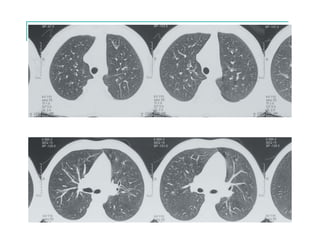

EVOLUCIÓN RADIOLÓGICA

ESCOLARES

- Infecciones respiratorias recurrentes

- Bronquiectasias

- Escaso desarrollo ponderal

- Malabsorción

- Tos crónica

- Cultivo de esputo con Staphylococcus o Pseudomonas

- Pólipos nasales

ADOLESCENTES

- Reagudizaciones respiratorias frecuentes

- Compromiso de V.A.S. (rinosinusopatía y pólipos)

- Atelectasias

- Hemoptisis

- Neumotórax